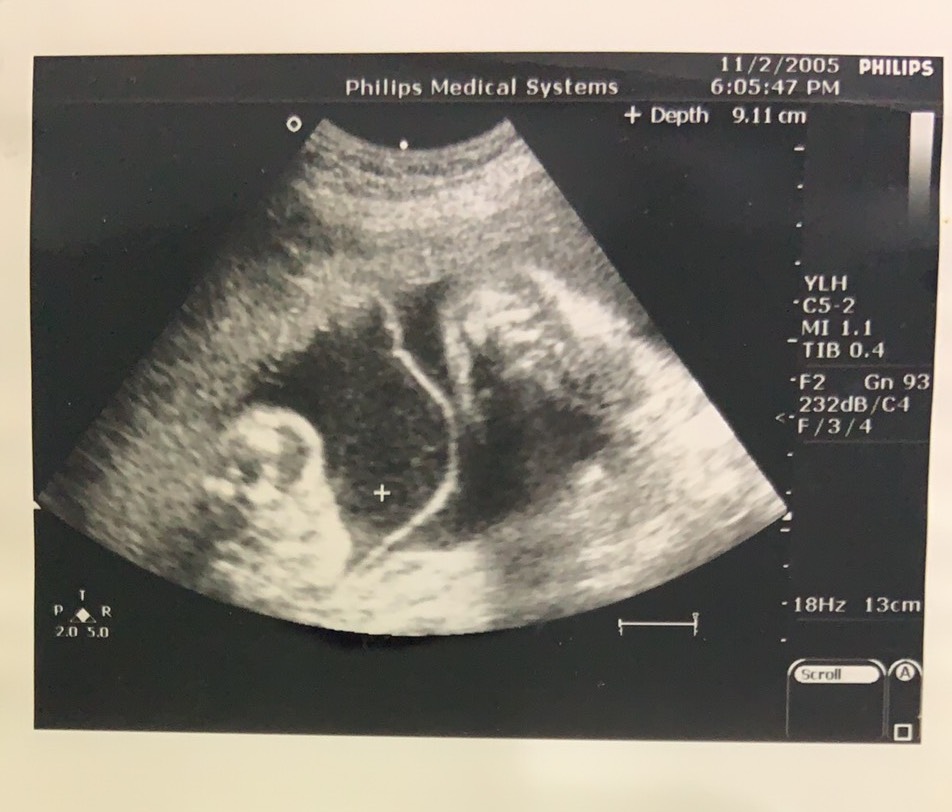

16年前經李茂盛醫師之手誕生的高家姊妹子蕎、子璨,如今已長大成亭亭玉立的高中生,兩姊妹回想起小學時期,有天媽媽拿了診斷書及胚胎的照片,並告訴他們試管寶寶的身份,姐姐子蕎表示:「小學時懵懵懂懂,直到國中的生物課,聽到老師介紹試管嬰兒的技術,才讓我意識到原來自己的出生是這麼特別!」。在一次職業訪談的機緣下姊妹倆與李茂盛醫師會面,聽聞李茂盛醫師行醫三十餘年,仍秉持「視病猶親」的理念,感性的道:「如果沒有試管嬰兒的技術、沒有李醫師,就沒有現在的我們。我們以身為試管寶寶為榮。」高一生的子蕎、子璨,已對未來職涯規畫非常有目標;妹妹子璨的目標是跟隨媽媽腳步,投身教育領域當國小老師;而姐姐子蕎的興趣則在數理生物方面,在國中會考還拿得全校唯一的5A++作文六級分,學業成績表現非常亮眼,並以考取醫學系為目標,也因為自己就是試管寶寶的身份,更燃起想追隨李茂盛醫師腳步投身不孕症領域的熱忱,透過專業的傳承讓生命延續。